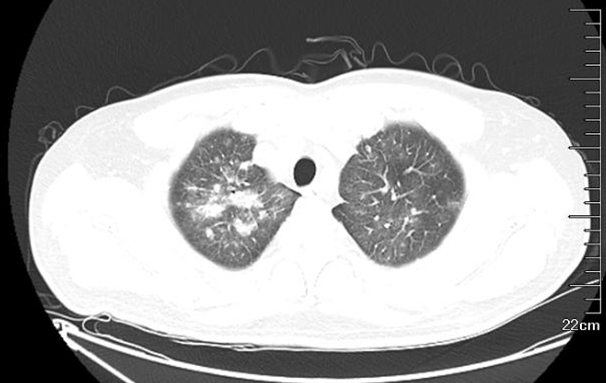

患者于2018年5月9日无明显诱因出现畏寒发热、最高可达39℃,伴咳嗽,偶有咳痰,为白色黏痰,无头晕头痛,无胸闷胸痛,无呼吸困难,无腹胀腹痛。2018年5月10日就诊于当地医院,门诊血细胞分析:白细胞计数0.31×109/L;尿红细胞形态计数:尿蛋白(+);生化+电解质:谷草转氨酶63 IU/L,肌酐109 μmol/l。遂予以克林霉素联合利巴韦林抗感染1周,期间症状未缓解,仍间断发热。于5月18日调整为头孢哌酮/舒巴坦联合左氧氟沙星抗感染,仍无效,体温最高达39℃。为求进一步诊断,来我院,门诊胸部HRCT平扫如图1所示:①两肺多发感染,两肺上叶为著;②甲状腺左叶小结节,建议B超检查;③附见:轻度脂肪肝;双侧肾上腺结节样增粗。拟“发热查因:社区获得性肺炎”收入院。病程中,患者食纳、睡眠可,大小便正常,近期体重未见明显增加或减轻。

图1  胸部CT:两肺多发感染,两肺上叶为著